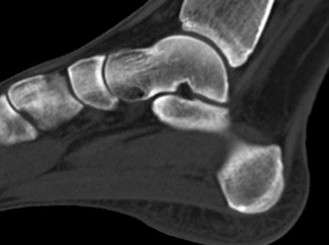

Question 6

A 45-year-old manual laborer presents with chronic radial-sided wrist pain, recalling a fall on an outstretched hand 5 years ago. Imaging shows a scaphoid nonunion with radioscaphoid and capitolunate arthritis, but the radiolunate joint remains completely preserved.

This describes which stage of Scaphoid Nonunion Advanced Collapse (SNAC), and what is a standard surgical option?

Explanation

The progression of SNAC wrist is predictable. Stage 1 involves arthritis at the radial styloid; Stage 2 involves the entire radioscaphoid joint; Stage 3 involves the capitolunate joint; Stage 4 involves the radiolunate and/or entire carpus. Because the radiolunate joint is preserved in Stage 3, a four-corner fusion (capitate, hamate, lunate, triquetrum) with scaphoid excision is the standard salvage procedure. Proximal row carpectomy is contraindicated due to capitolunate arthritis.